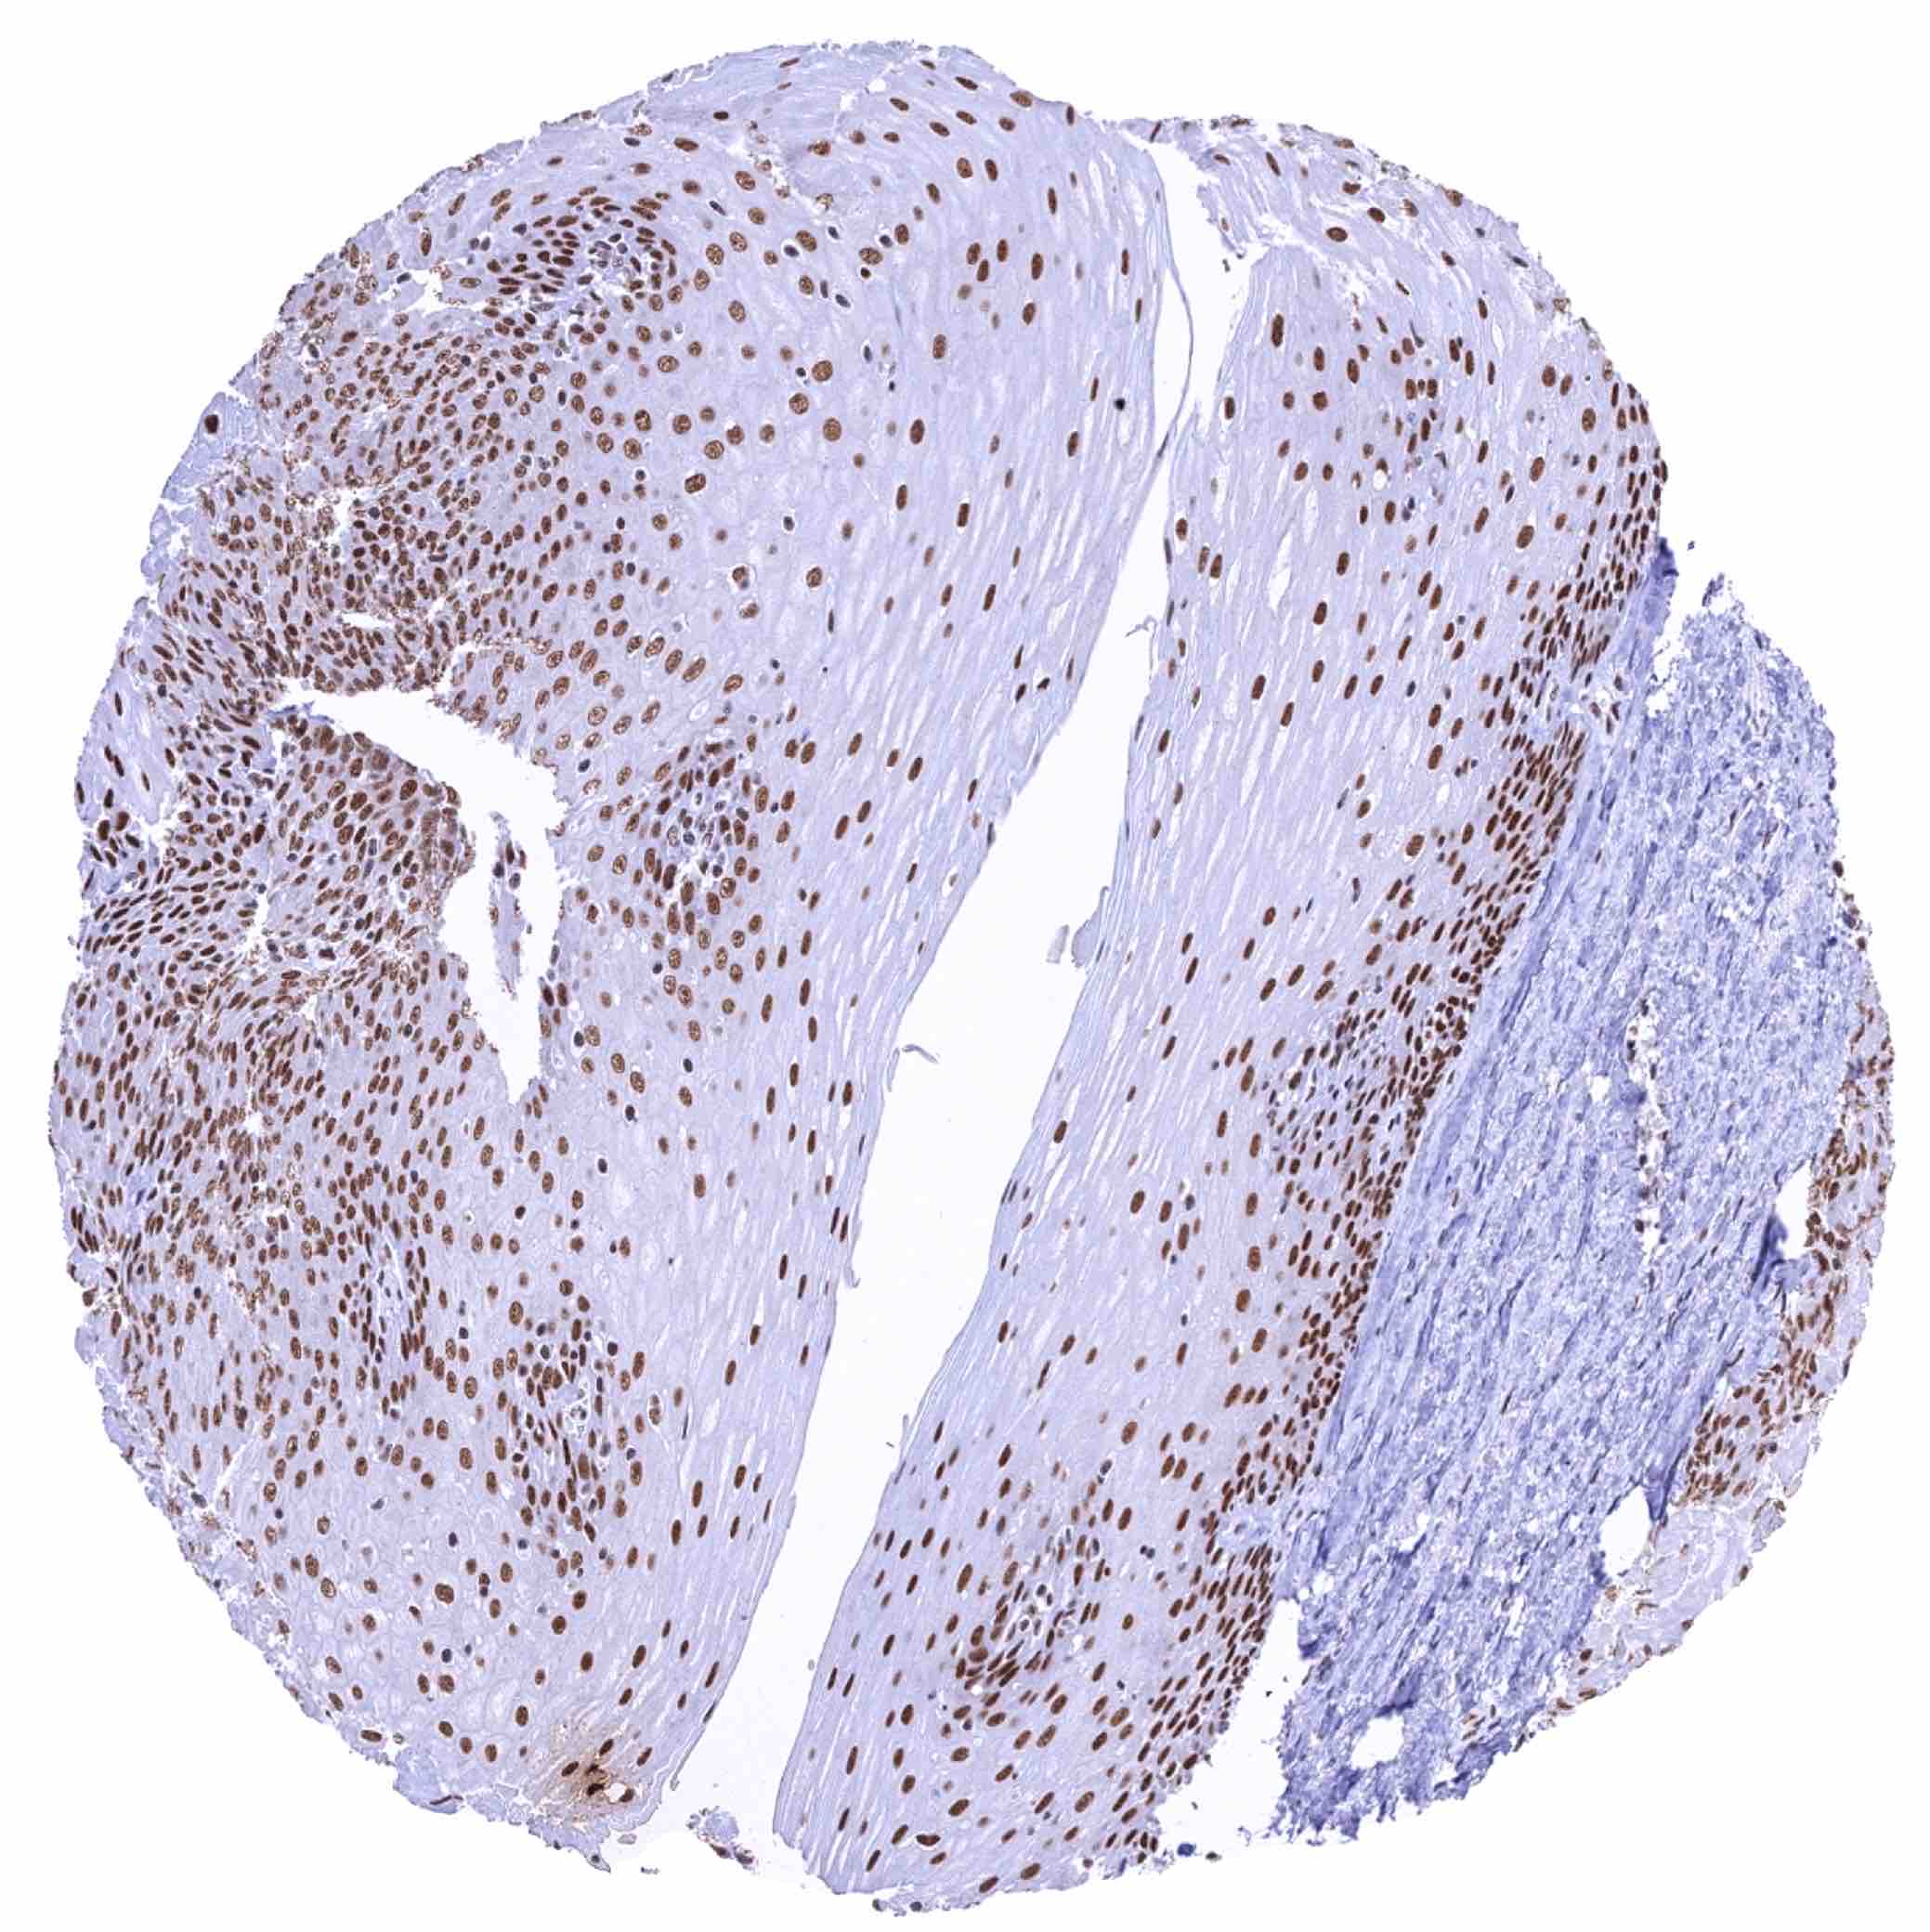

Uterus, myometrium – Moderate to strong nuclear KDM6A staining of muscular cells